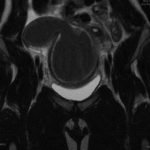

Due to pain out of proportion to her exam, an ultrasound of her pelvis was obtained and showed a blood-filled distended uterus, or hematometrocolpos (white arrow), with a 4.9 cm right ovarian cyst (blue arrow). A pelvic magnetic resonance imaging (MRI) then revealed an obstructed right hemi-vagina, normal left uterus and vagina and ipsilateral renal agenesis (red arrow) with normal left kidney (double arrow) consistent with obstructed hemivagina, ipsilateral renal agenesis (OHVIRA) syndrome. The patient underwent surgical repair with complete resolution of symptoms.